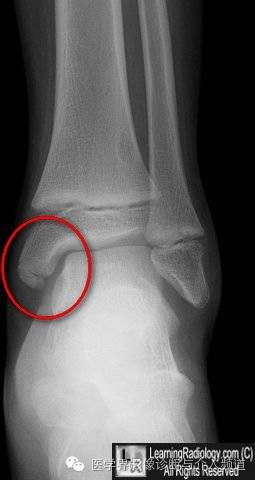

1、胫骨内踝骨骺:胫骨内踝的骨骺有多个骨化中心并非少见,特点是边缘光整,骨皮质连续,不确定时可做双侧对比。

不确定时可做双侧对比